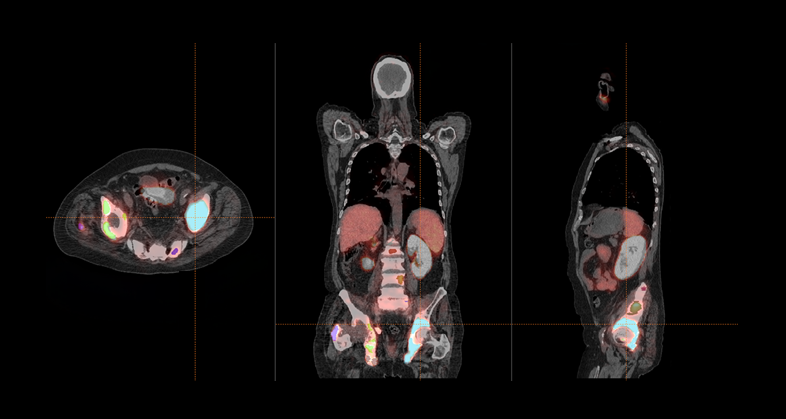

We provide automated segmentation methods for lesions and organs in whole body PET/CT examinations. The most frequent clinical scenarios are lymphoma and multiple myeloma, extracting lesion-level features, which, combined at the patient level, can help in predicting treatment response in standard or advanced therapies as well as other phenomena like cytokine release syndrome (CRS) or Immune effector cell-associated neurotoxicity syndrome (ICANS) in cell therapies such as Chimeric Antigen Receptor T-cell therapies (CAR-T).